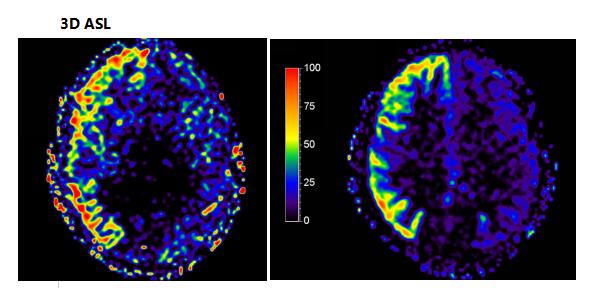

中枢神经系统应用

可应用于颅内外肿瘤性病变,脑卒中病变、血管性病变、感染性病变、外伤性病变,脑白质病变,先天性发育异常、退行性病变等中枢神经系统疾病检查,尤其是脊柱及脊髓病变,同时可以全脊柱成像,整个脊柱及脊髓病变一览无余,无处藏身。

血管方面应用

可以采用注射造影剂血管成像,也可以通过TOF、PC、TRANCE等方法进行无造影剂血管成像,无骨伪影,图像清晰,身体各部位血管均可成像。